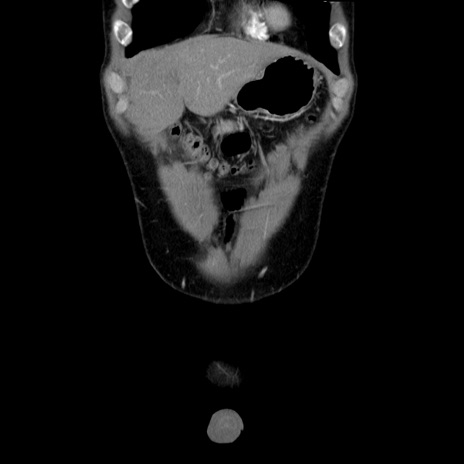

症例36(冠状断像)

【症例】20歳代 男性

【主訴】心窩部痛

【現病歴】今朝より上腹部痛あり。一旦軽快していたが再度出現したため救急要請。昨日夕に白身の魚を含む刺身を食べた。

【身体所見】BP 136/89mmHg、HR 74/min、BT 37.0℃、腹部:膨満、軟、心窩部に圧痛あり。反跳痛なし、筋性防御なし、腸雑音やや亢進あり。

【データ】WBC 17700、CRP 0.48